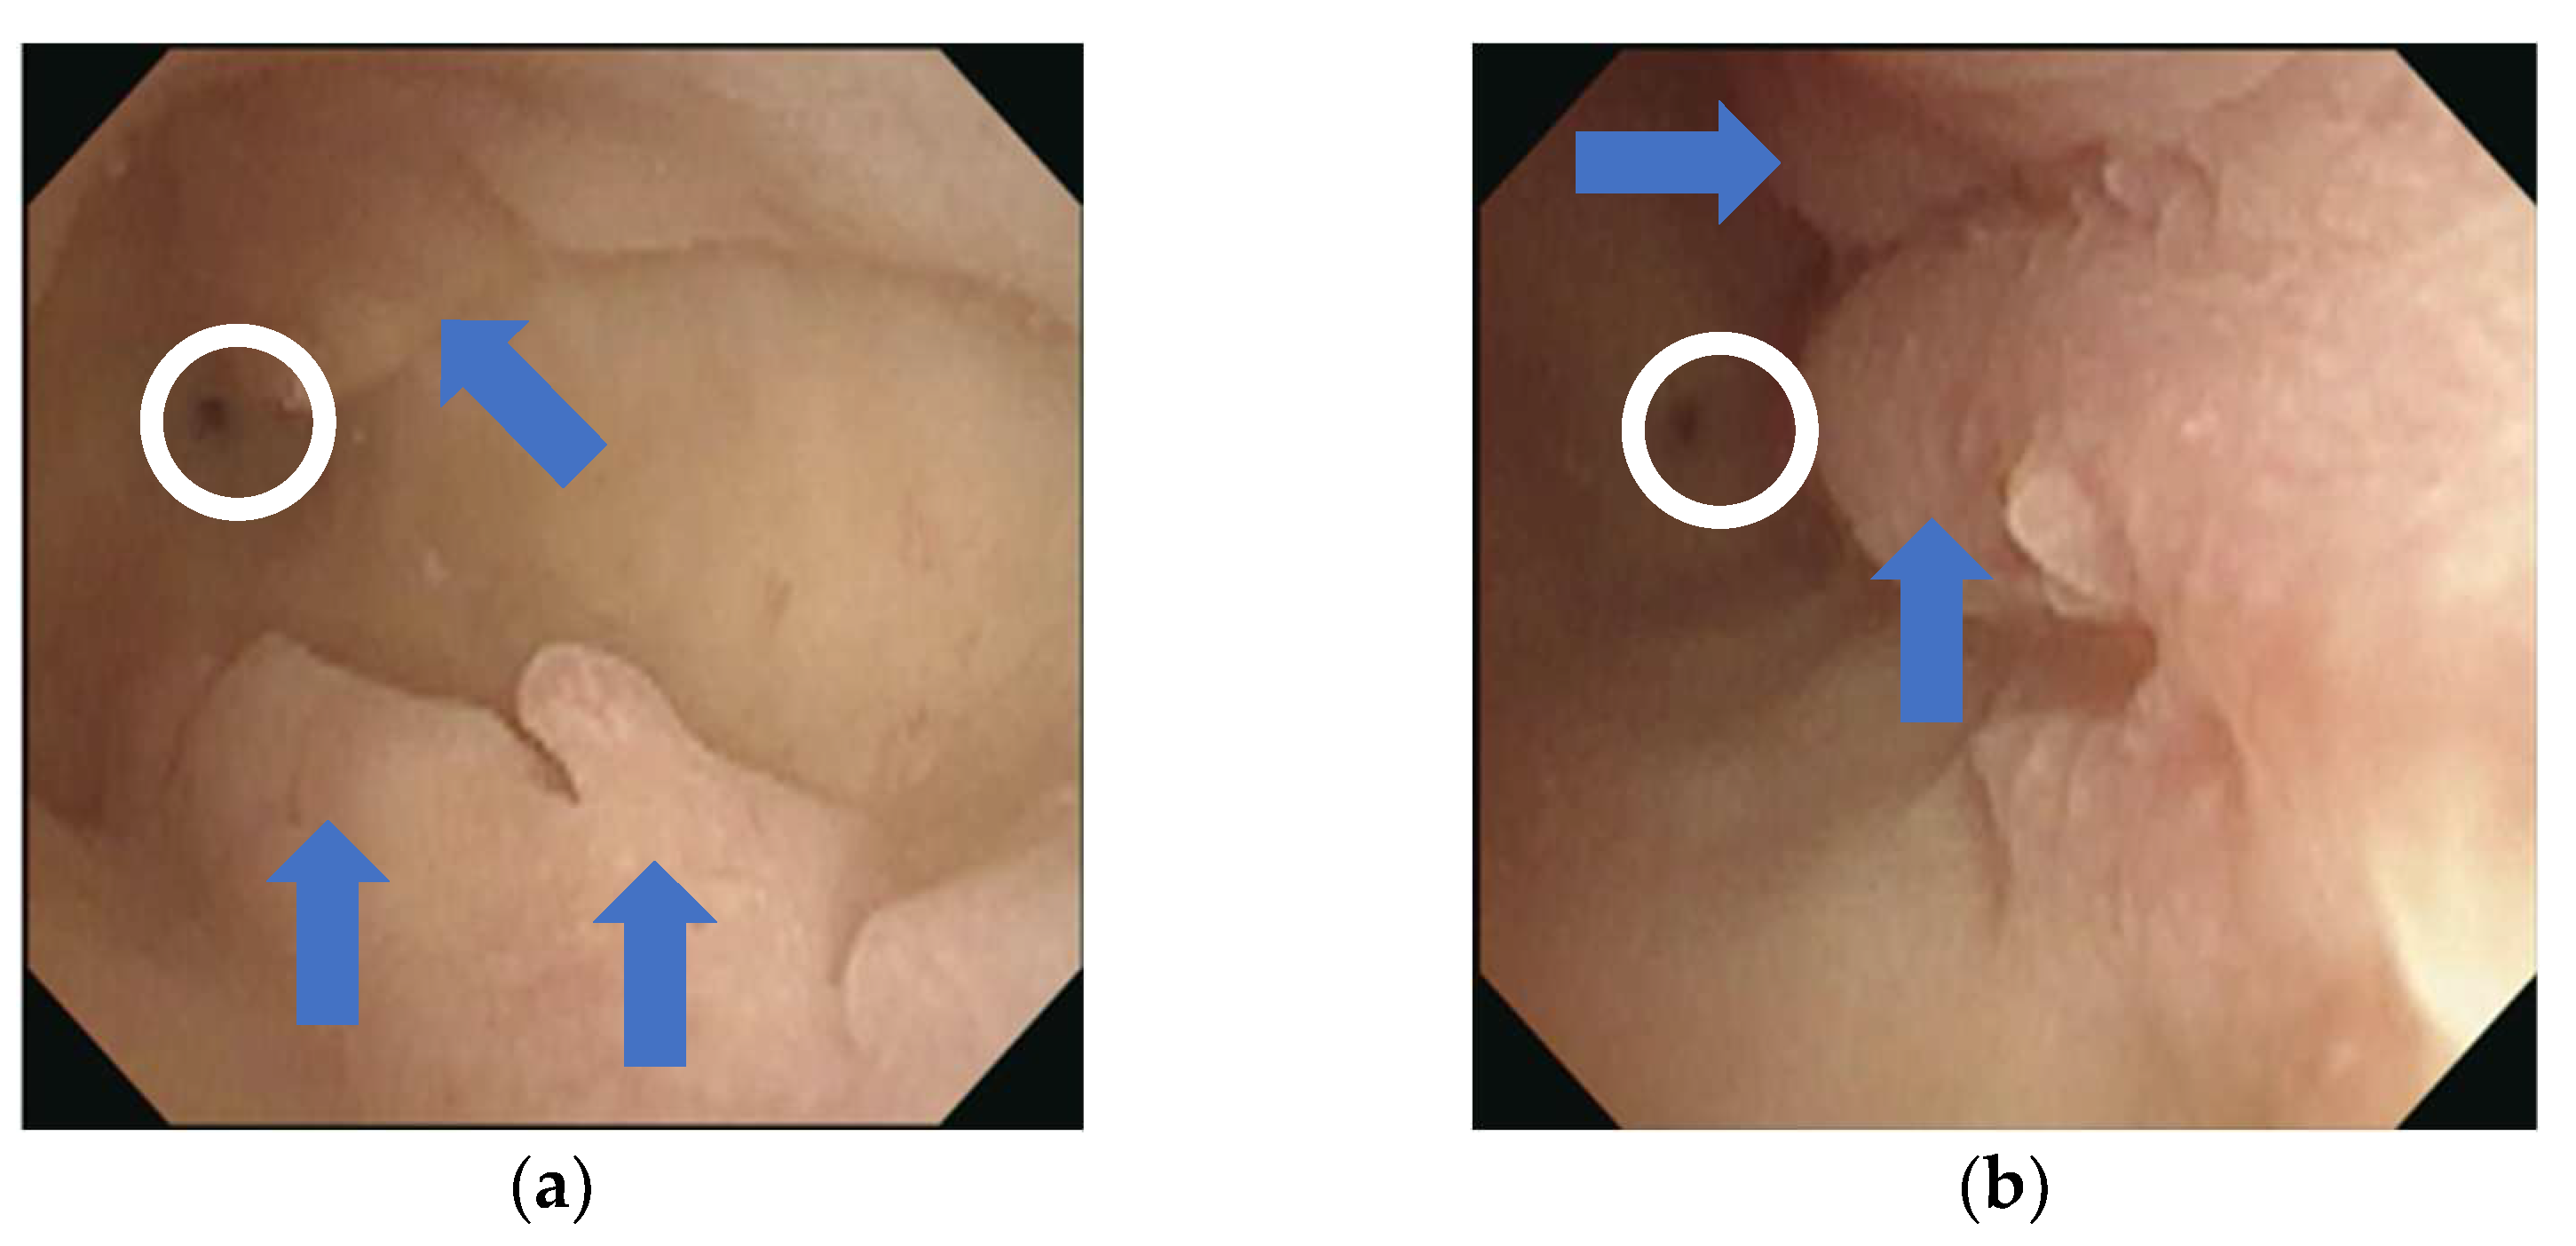

2. Case Presentation